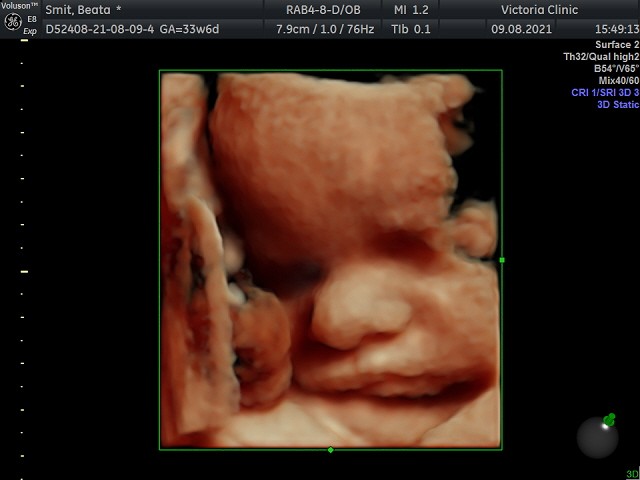

Jestem po wizycie u nowego lekarza. Po raz pierwszy od długiego czasu poczułam wewnętrzny spokój i wiarę w to, że wszystko jest dobrze :) Mały podgonił z wagą - obecnie waży 2300g, a jego orientacyjna waga urodzeniowa to 3500, o ile dotrwam do 40 tygodnia :) Widziałam go w 4d jak się ruszał, wystawiał język, a nawet uśmiechał się!!! To było niesamowite, byłam bardzo wzruszona. A ze słabszych wiadomości - na koniec udzieliły mu się akrobacje i już nie jest gotowy do wylotu główką do dołu... Lekarz mówi, że mam sporo wód płodowych i raczej powinien się jeszcze przekręcić ;)

Załączniki

• IMG_20210809_1_8.jpg

IMG_20210809_1_8.jpg

40,2 KB · Wyświetleń: 88